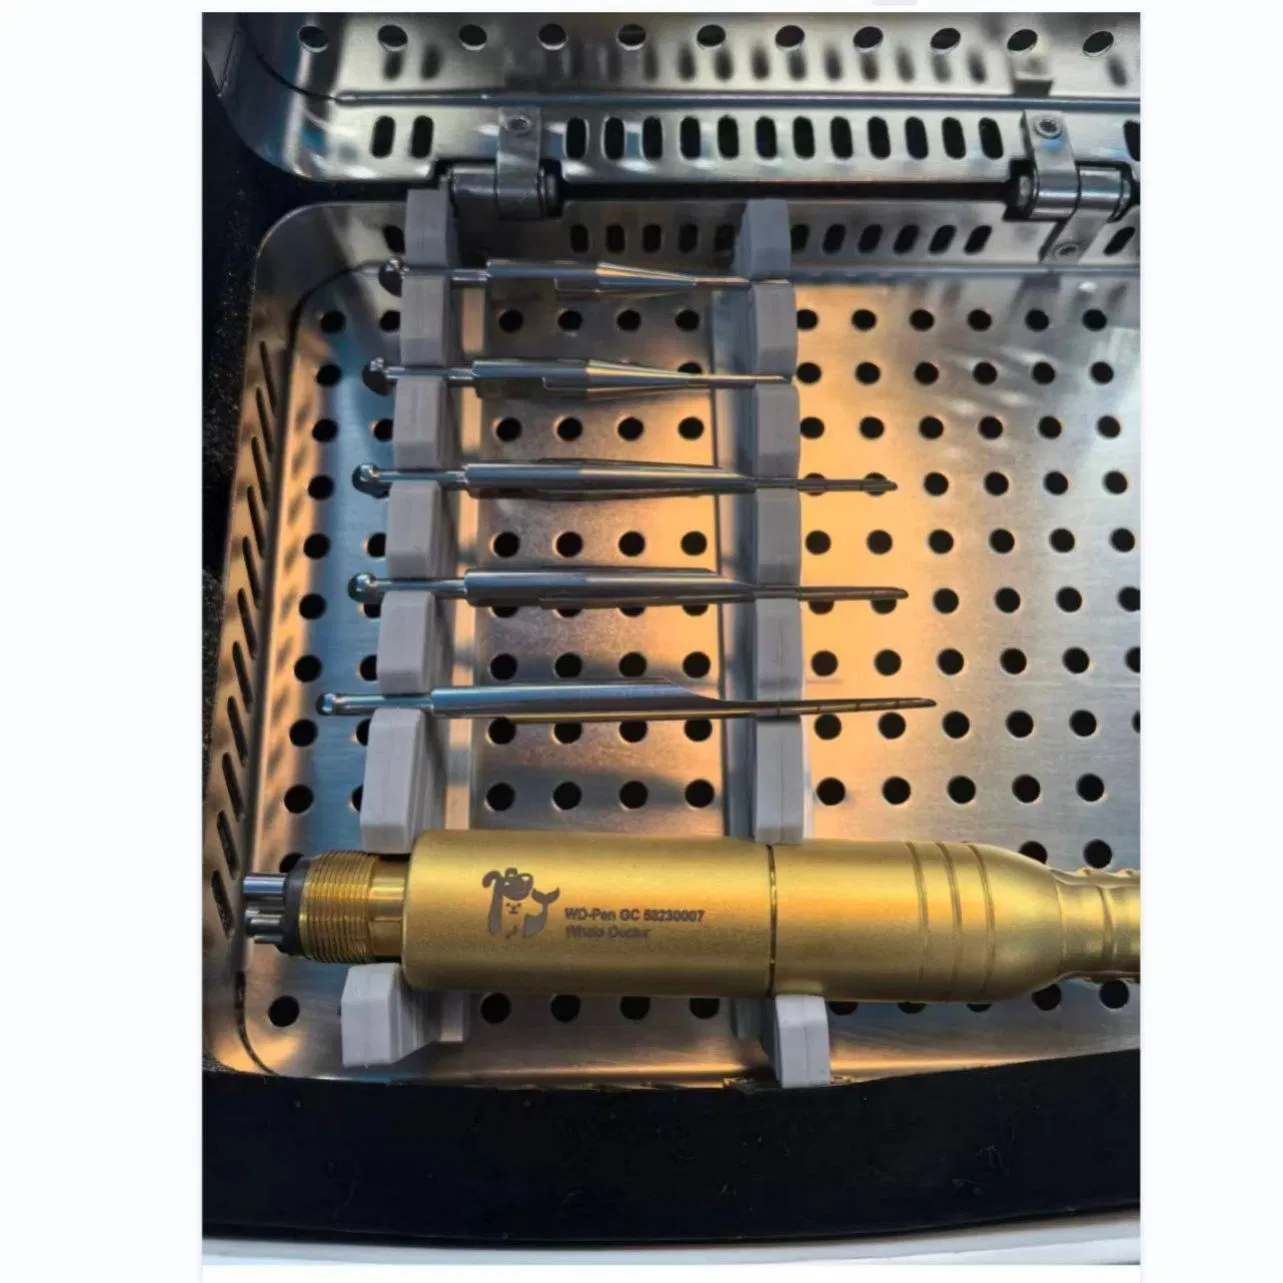

This study evaluated the effectiveness of state-of-the-art dental tools for veterinary use. The treatment group utilized the revolutionary Pneumatic Dental Elevator Kit. Critical factors observed included physiological parameters, intraoperative complications, extraction duration, and socket damage. Rigorous statistical analysis highlights the superior performance of these advanced tools.